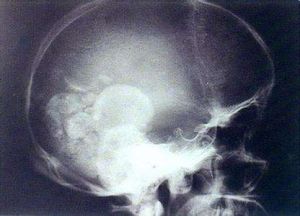

4.頭顱攝片、CT、腦血管及脊髓造影可發現病變和阻塞部位。CT平掃圖像在急性期表現為腦水腫腦實質可見大小不一、程度不等的低密度水腫區,腦室狹小,造影后不增強;在囊腫期則出現高密度的占位病變表現,但邊界不清,增強掃描病灶有強化;纖維瘢痕期則表現為鈣化灶。在MRI影像中T1加權表現為中央高信號或等信號、外周低信號的病灶,T2加權則表現為中央高信號周邊低信號的病灶。

腦型患者在痊癒過程中腦內病變可形成鈣化灶,結合臨床及CT等的檢查結果,有助於定位診斷。這些患者難以從痰、糞及胃液中找到蟲卵,但免疫學檢查仍呈陽性反應。